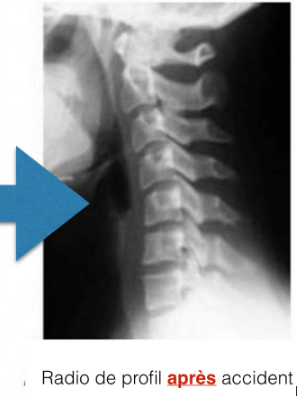

Une fois que les cervicales sont devenue raide et droite comme sur la radio après accidents en exemple est ce qu’il y a un moyen de faire revenir les cervicales dans la bonne courbure?

J’ai 24 ans et cela fais plusieurs années que j’ai des douleurs cervicales. Ayant changer de médecins celui ci m’a dis de passer une radio ( enfin !) Et résultat mes cervicales sont droites raide, la radiologue me dis que j’ai des contracture musculaire ok mais depuis des années ? Malgres les médicaments décontractant anti-inflammatoire et tout le reste…. ( je précise ces traitements non pas étais pris pour les cervicales mais d’autres problème de santé)